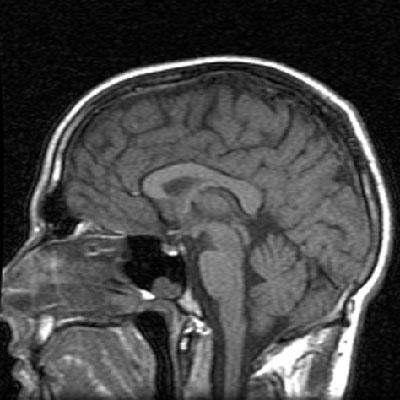

A sagittal T1-weighted magnetic resonance image of my head, highlighting my corpus callosum and brainstem An axial T1-weighted MR slice showing my basal ganglia and frontal and parietal lobes

A sagittal T1-weighted magnetic resonance image of my head, highlighting my corpus callosum and brainstem